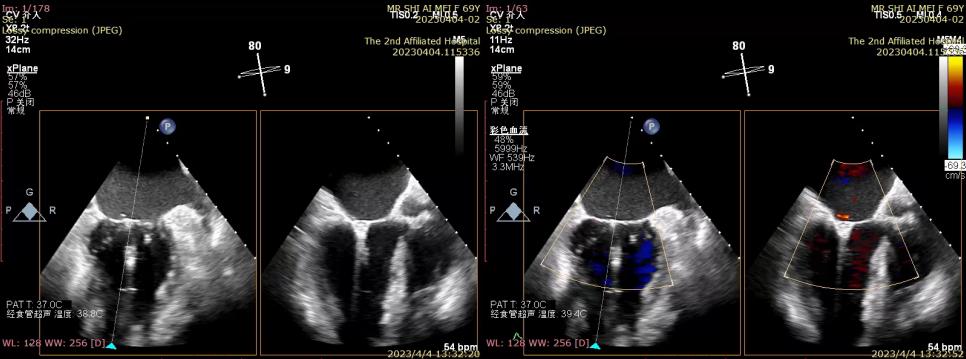

完全在超声引导下完成二尖瓣夹的定位、瓣叶抓取和二尖瓣夹的释放

三维超声确认夹合位置理想